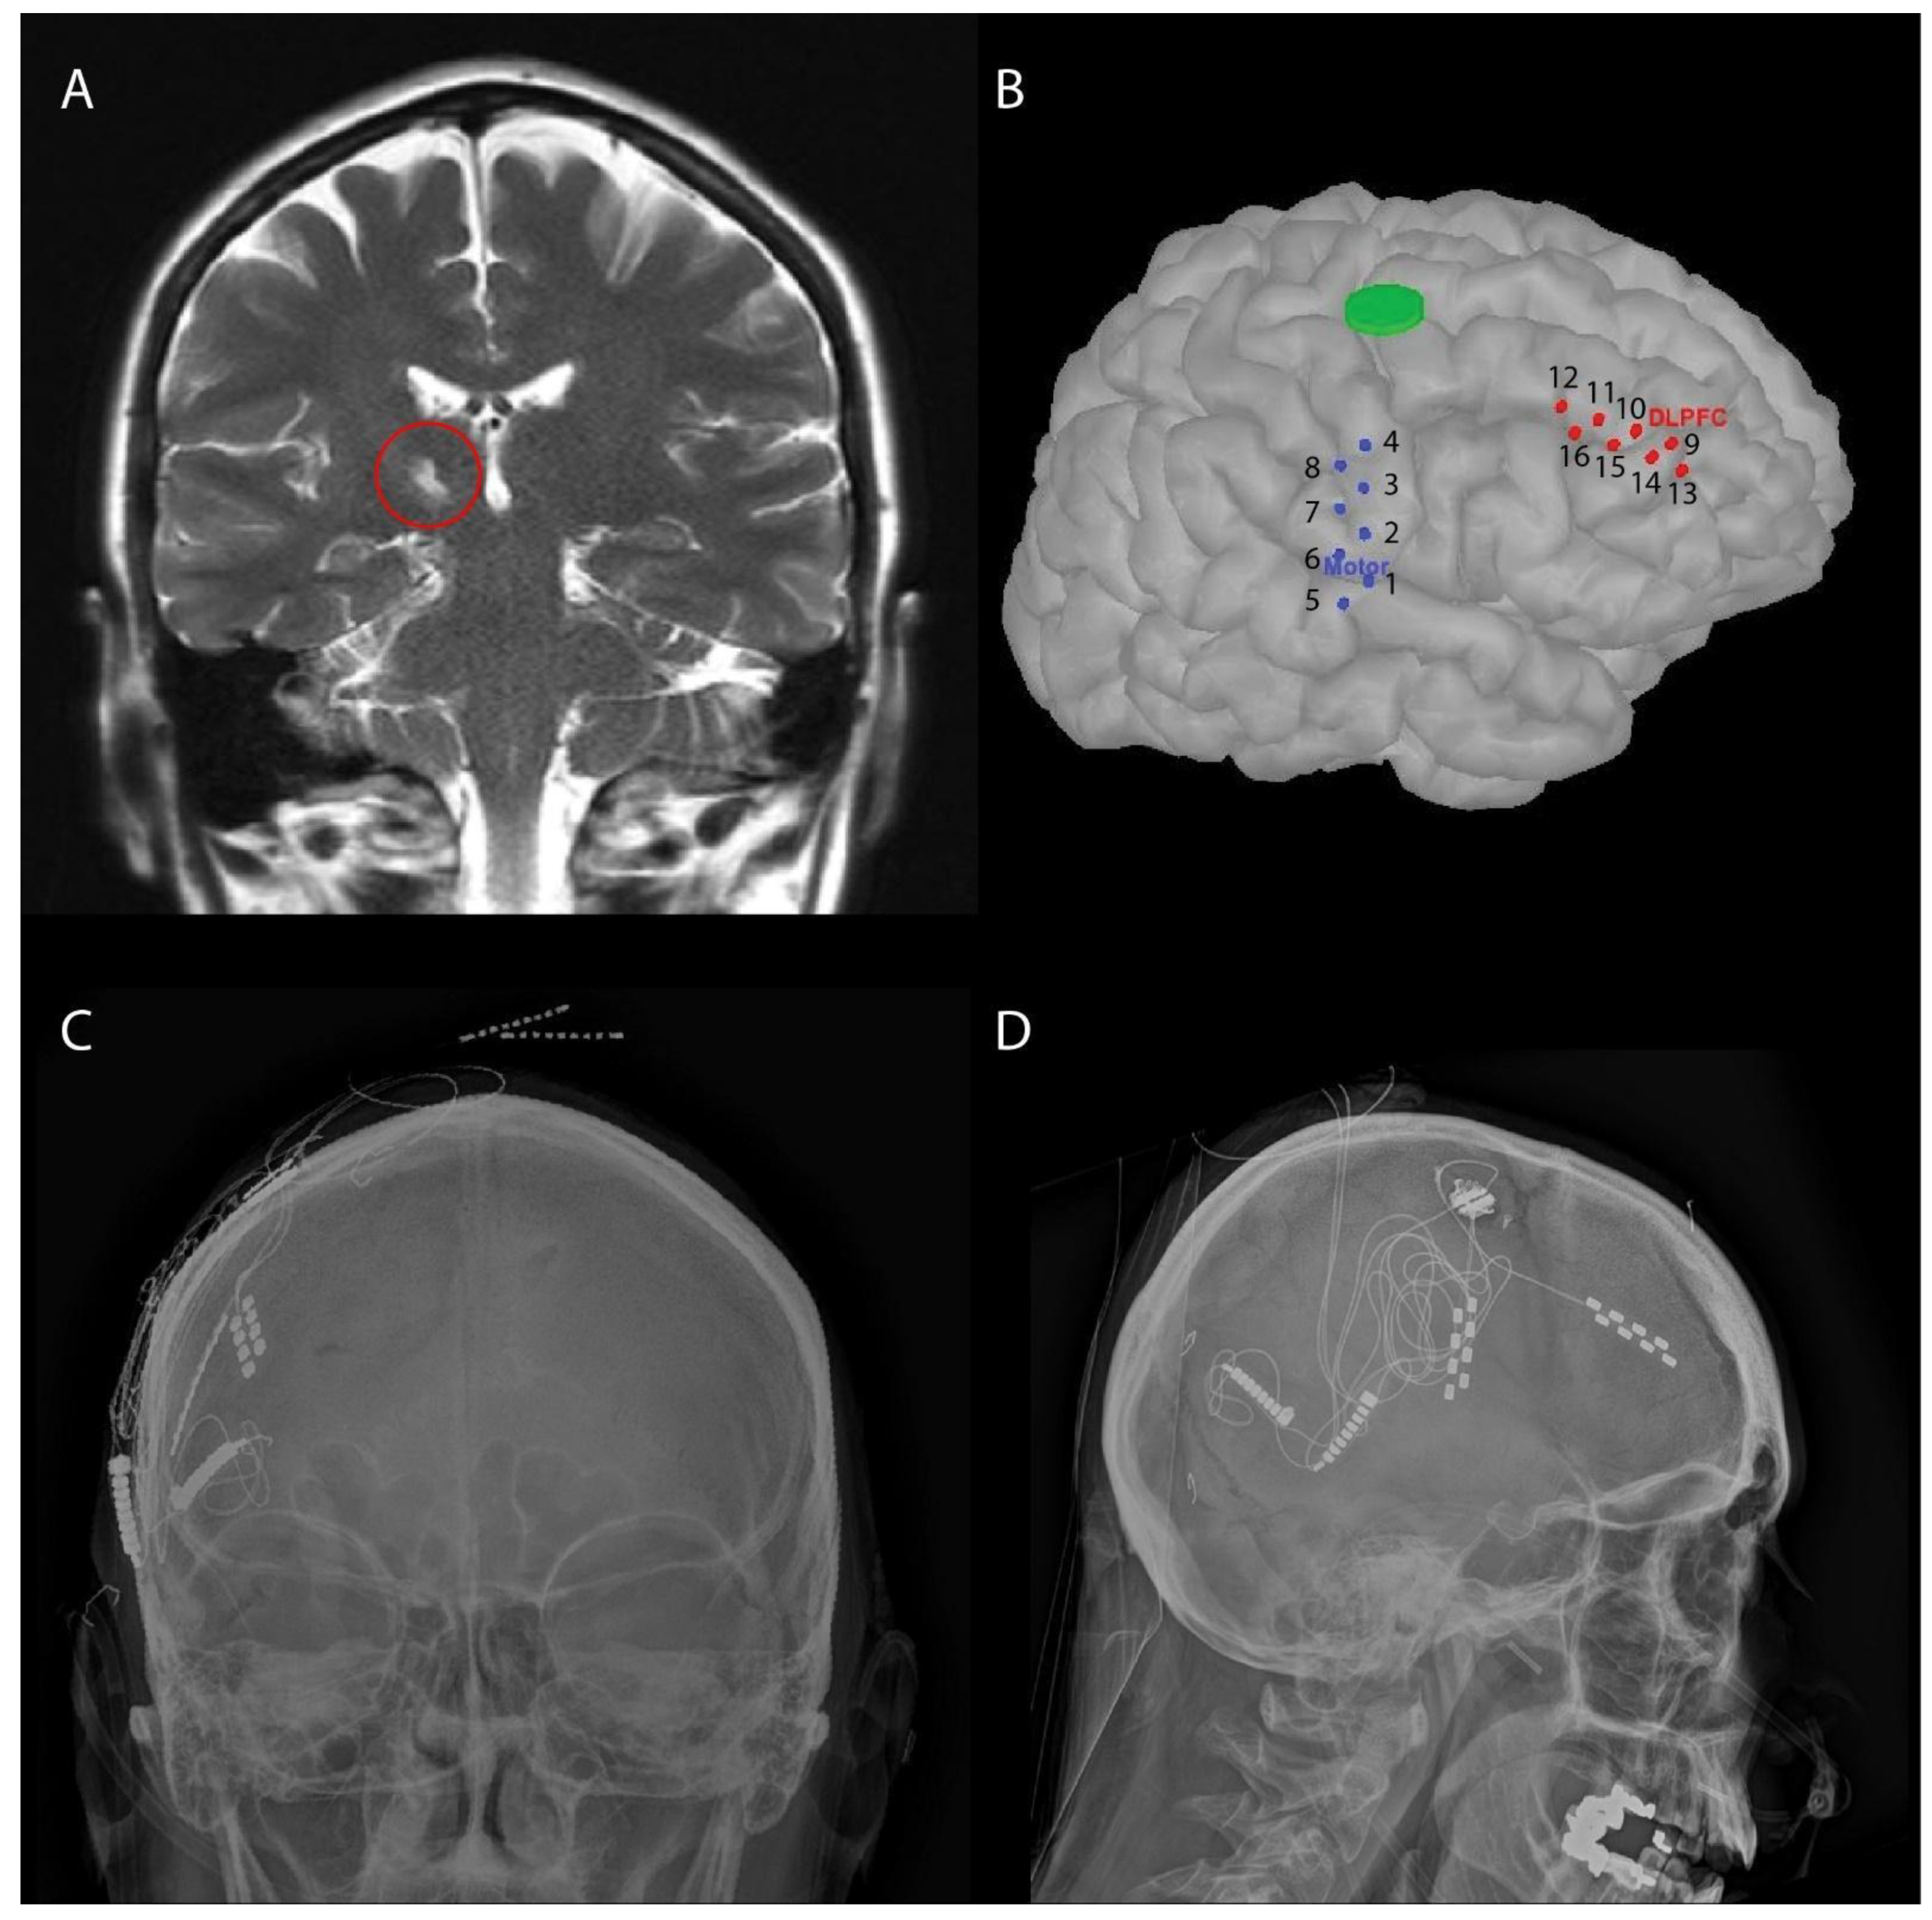

2.2. Surgical Procedure: Placement of Subdural Electrodes and Externalization